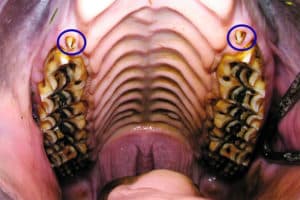

Equine Wolf Teeth

While these teeth usually don’t pose a health risk to the horse, they are often removed in performance horses.

While these teeth usually don’t pose a health risk to the horse, they are often removed in performance horses.